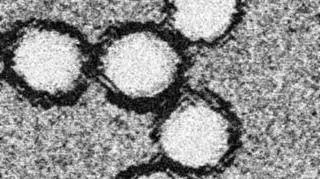

Wirus pod mikroskopem elektronowym

Źródło: Wikipedia